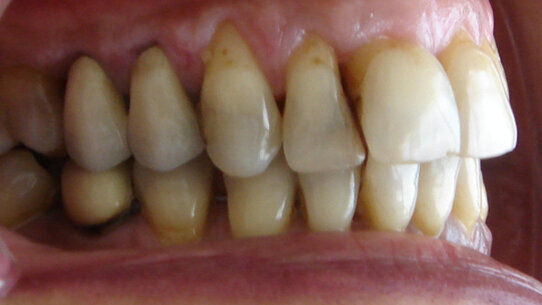

Discrepanze dei margini gengivali

Possono essere provocate o da una abrasione del margine gengivale o da una migrazione del tessuto gengivale. I fattori responsabili delle recessioni gengivali sono la malattia parodontale, l’accumulo di placca, terapie parodontali e traumi da spazzolamento. Un modo per ridurre la recessione gengivale è il controllo della placca oppure un’appropriata chirurgia parodontale. Allo stesso tempo, alcuni autori hanno proposto l’uso di forze ortodontiche per ridurre la recessione.

Uno studio effettuato su 28 pazienti da Re e collaboratori29 ha avuto lo scopo di valutare gli effetti combinati della chirurgia parodontale con intrusione dentale per ridurre la recessione parodontale attorno all’incisivo centrale superiore e, in secondo luogo, per verificare se un biotipo parodontale spesso o sottile risponde differentemente.

I risultati hanno mostrato miglioramenti dalla fine della terapia al follow-up effettuato a 1 anno. In particolare, la maggior riduzione è stata di 0,96 mm sui siti buccali e di 1,71 sui siti mesiali. Non ci sono state differenze staticamente importanti per quanto riguarda il biotipo parodontale.

I clinici devono stabilire le cause della recessione per poter decidere il trattamento di elezione: movimento ortodontico per riposizionare il margine gengivale o correzione chirurgica delle discrepanze del margine gengivale.